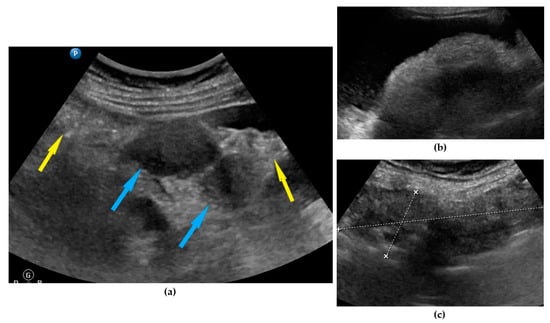

| Peritoneum, abdomen | Abdomen carcinomatosis manifest as hypoechogenic lesions over the peritoneal surface of the paracollic gutters or internal abdominal wall. | Figure 3 | Video S3 |

| Peritoneum, pelvis | Pelvic carcinomatosis manifests as hypoechogenic lesions over the peritoneal surface of the pelvic wall: laterally, in the pouch of Douglas (no rectum involvement) or the bladder in the uterine serosa. | Figure 4 | Video S4 |